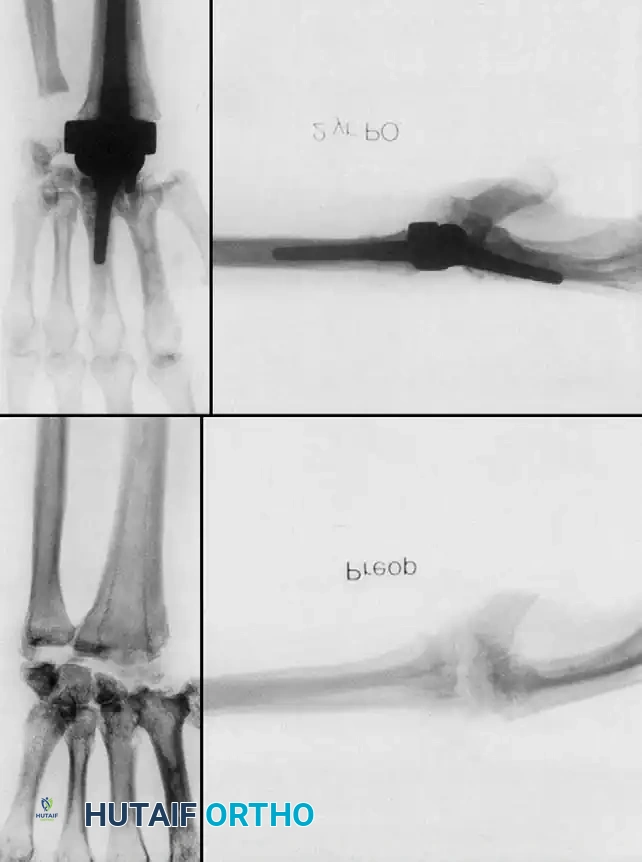

Silicone Implant Arthroplasty (Swanson)

Silicone spacer arthroplasty remains a viable option for low-demand rheumatoid patients with advanced disease (Stage III or IV) and poor bone stock that precludes the use of metal-on-plastic total wrist systems. The procedure requires minimal bone resection and acts as a dynamic spacer to maintain alignment while a fibrous capsule forms.

Image

While pain relief is initially excellent, surgeons must counsel patients on the high complication rates associated with silicone implants over time. Long-term studies indicate a prosthetic fracture rate ranging from 10% to 52%, and progressive radiographic settling with bone resorption in up to 75% of cases. Despite these radiographic failures, clinical satisfaction often remains acceptable in low-demand individuals.